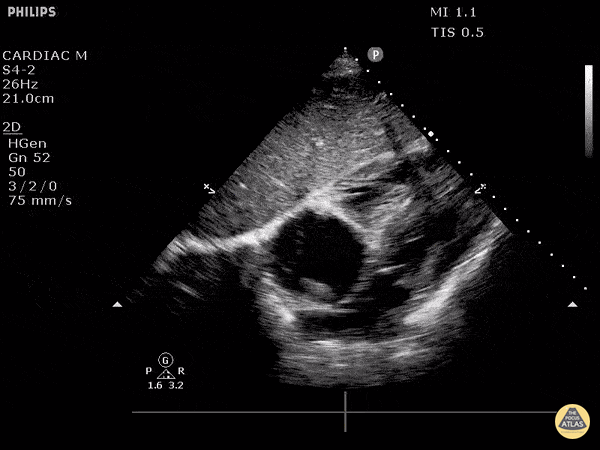

Other Cardiac Pathology - Clot Within Right Atrium

This patient initially presented post-operatively to the emergency department with complaints of dyspnea. From this subxiphoid view of the heart, we can see a hyperechoic structure suggestive of clot formation. An alternative view of this clot viewed from the right atrium and IVC junction can be seen here, termed “clot-in-transit”. The patient was subsequently diagnosed with a DVT that extended into their central femoral vein. Image courtesy of Robert Jones DO, FACEP @RJonesSonoEM Director, Emergency Ultrasound; MetroHealth Medical Center; Professor, Case Western Reserve Medical School, Cleveland, OH View his original post here